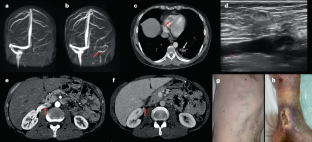

Behçet syndrome is a rare, chronic inflammatory disease of unknown aetiopathogenesis, most commonly presenting with mucocutaneous and ocular manifestations. Vascular involvement, most frequently superficial vein and deep vein thrombosis, can occur in up to 50% of patients with Behçet syndrome. Venous thrombosis at atypical sites (inferior and superior vena cava, suprahepatic veins with Budd–Chiari syndrome, portal vein, cerebral sinuses and right atrium and/or ventricle) and arterial involvement (mostly in situ thrombosis and aneurysms of the pulmonary arteries, as well as aneurysms of the abdominal aorta, and peripheral and visceral arteries) are also unique features of Behçet syndrome. Behçet syndrome is considered a natural model of inflammation-induced thrombosis in humans, with an impaired immune-inflammatory response rather than traditional cardiovascular risk factors contributing to thrombogenesis. Specifically, neutrophil hyperactivation and neutrophil-mediated mechanisms of damage directly promote endothelial dysfunction, platelet activation and thrombogenesis in Behçet syndrome. This unusual pathogenesis directly determines the treatment approach, which relies mostly on immunosuppressants rather than anticoagulants for treatment of thrombosis and for secondary prevention. This Review discusses the main histopathological, pathogenetic and clinical aspects of vascular Behçet syndrome, addressing their implications for therapeutic management. Future perspectives in terms of pathogenetic studies, disease monitoring and treatment strategies are also discussed.

Venous thrombosis at atypical sites (such as Budd–Chiari syndrome, inferior and superior vena cava, and cerebral venous sinus thrombosis), and pulmonary and non-pulmonary artery involvement are also unique features of Behçet syndrome.

Seyahi, E. et al. Pulmonary artery involvement and associated lung disease in Behçet disease: a series of 47 patients. Medicine 91, 35–48 (2012).

Hamuryudan, V. et al. Pulmonary artery aneurysms in Behçet syndrome. Am. J. Med. 117, 867–870 (2004).

Mehdipoor, G., Davatchi, F., Ghoreishian, H. & Arjmand Shabestari, A. Imaging manifestations of Behcet’s disease: key considerations and major features. Eur. J. Radiol. 98, 214–225 (2018).